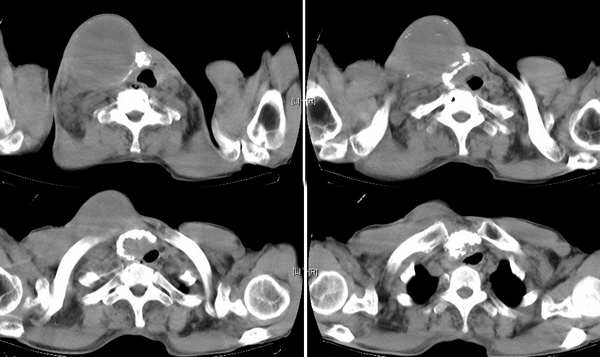

男,74岁,甲状腺肿30余年。现右颈部出现新肿块,疼痛,感乏力。

右颈部巨大软组织肿块影,范围较广,上至下颌角,下至颈静脉切迹。其最大层面位于右侧甲状腺区。肿块密度不均,其中有坏死液化区和班片状钙影,增强扫描见肿块实质区有强化。邻近结构挤压移位,部分结构侵蚀破坏,右侧多个颈深淋巴结肿大。两肺弥漫分布小结节影,以胸膜下为主,其大小不等,边缘光整。右侧胸壁亦见软组织结节影,纵隔多个淋巴结肿大及两侧锁骨上淋巴结肿大。

意见:右侧甲状腺癌并两肺、胸壁、纵隔淋巴结、颈深淋巴结、锁骨上淋巴结等广泛转移。